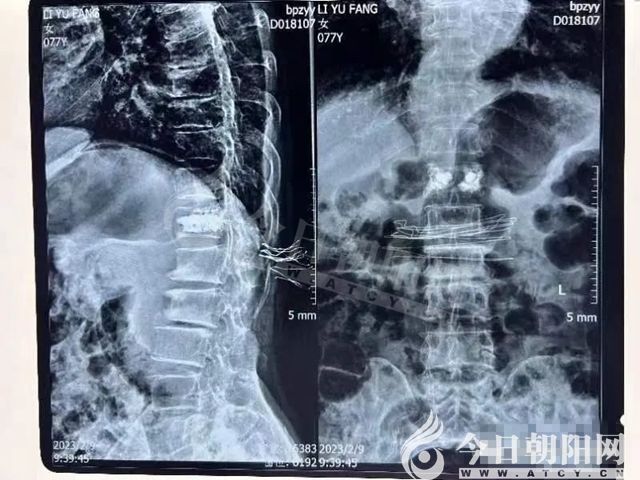

老人今年77歲,走路時(shí)不慎跌倒,摔傷腰部,導(dǎo)致第12胸椎壓縮性骨折,疼痛難忍,不能站立行走,兒女們不忍心看著老人如此痛苦,便來(lái)到醫(yī)院治療。

手術(shù)在局麻下進(jìn)行,恢復(fù)椎體,注入骨水泥固定,手術(shù)僅僅半個(gè)多小時(shí)就完成了。術(shù)后患者疼痛的癥狀很快消失,雙下肢完全恢復(fù)了正?;顒?dòng),術(shù)區(qū)僅留下2個(gè)穿刺的小針眼兒。